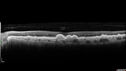

70-year-old Left eye worse than the right. Both eyes see distortion in the amsler grid for a few months

HTN, High Lipids, Osteoporosis

Meds: Lutein once daily, Calcium, Fish oil, Red Yeast Rice, CoQ10, Magnesium, MVI, Xanax

VA 20/16 OU

2+NS cataract